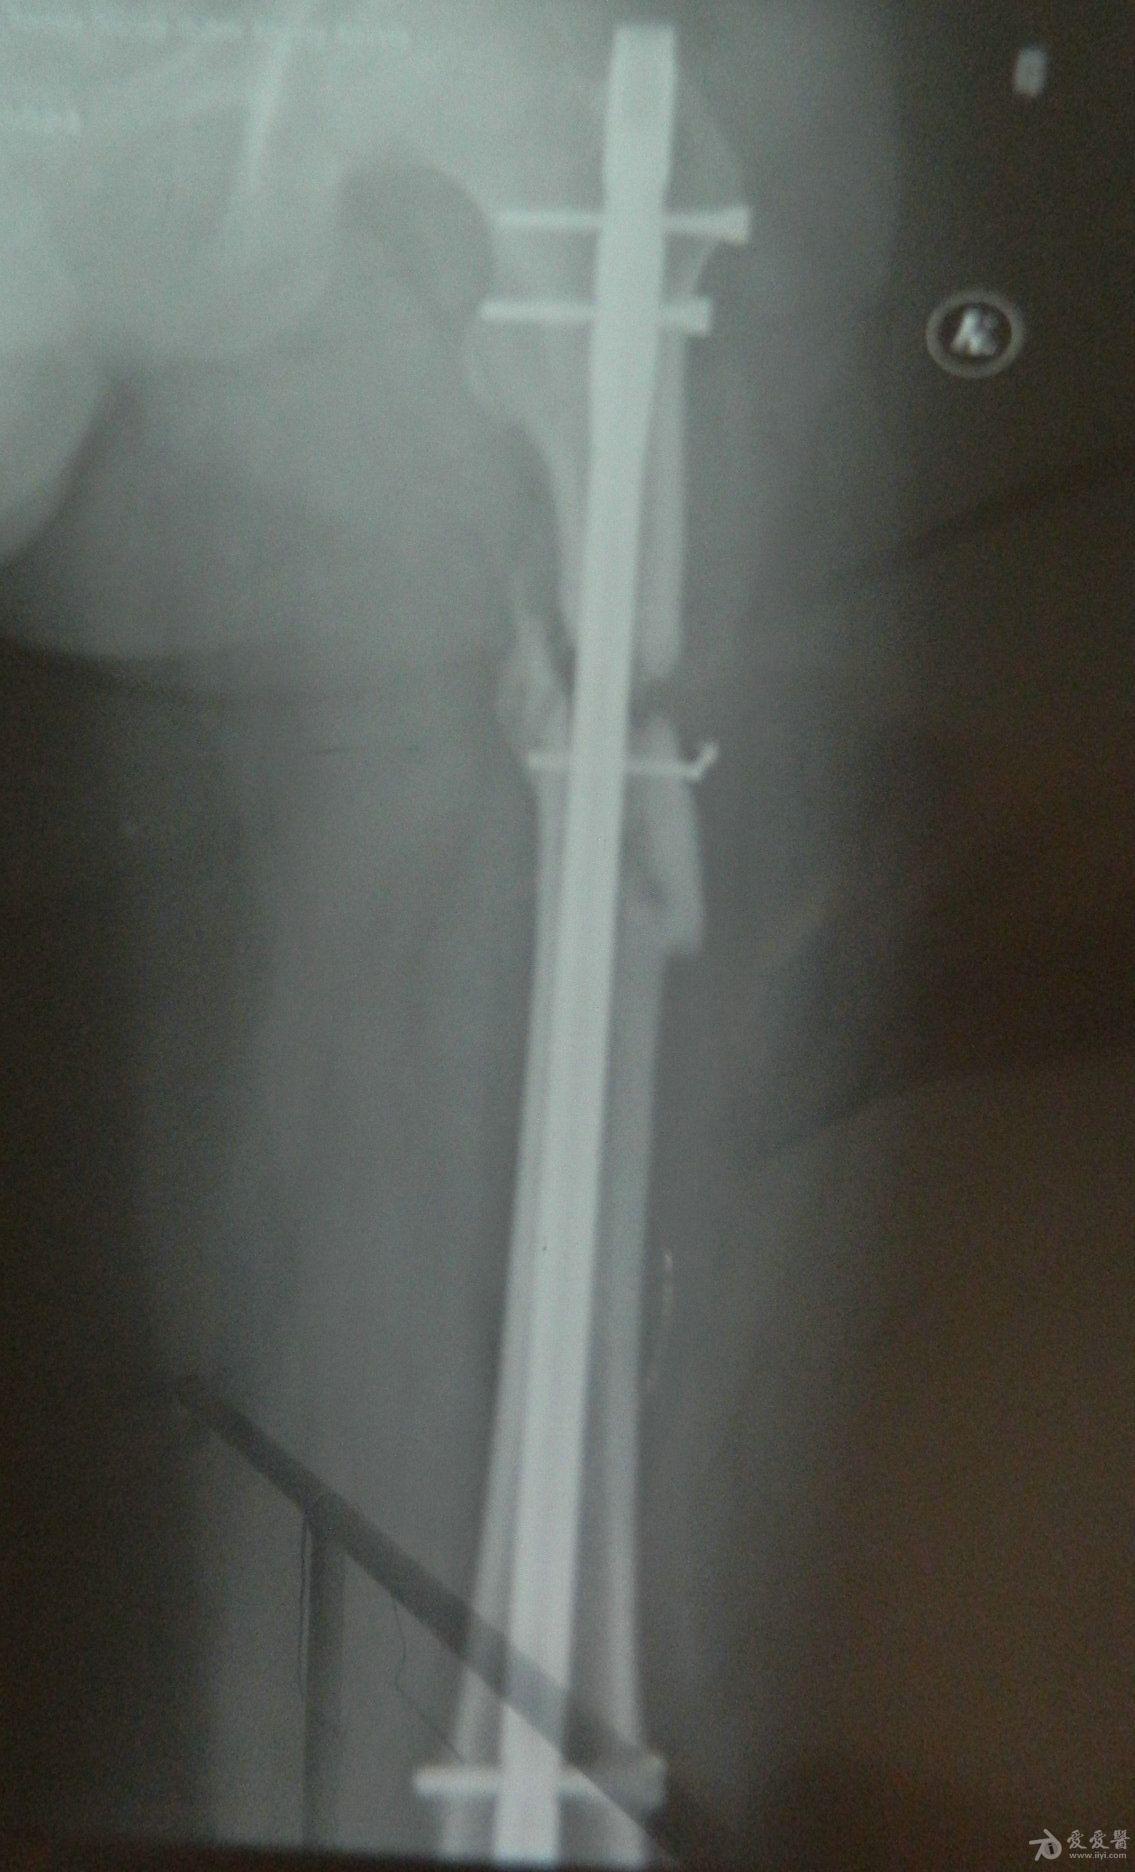

骨骨干骨折长好后图片,大腿骨干骨骨折恢复图

x光侧位显示胫骨骨干骨折

股骨干骨折术后骨不愈合 附图

大腿骨干骨骨折恢复图

股骨干骨折图片